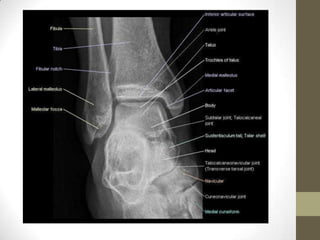

ANKLE JOINT

RADIOGRAPHY

By Dr. Nikhil Murkey